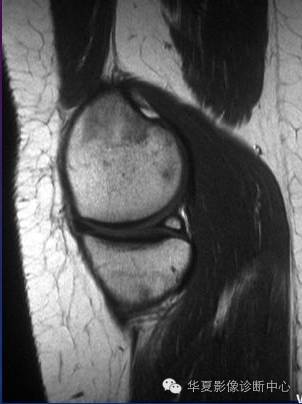

半月板小骨

半月板小骨少见,包埋在半月板内,X线片上与游离体难于区分。透视有助于与游离休鉴别。关节切开或关节镜检则可确诊。患者均诉周期性膝部不适和疼痛,肿胀和绞锁,常规X线上部分可显示膝部内侧有一小骨性结 构。MR影像上,半月板小骨位于内侧半月板后角,有清晰的低信号边缘。小骨显示的信号强度与正常骨髓相同:T1WI呈高信号;T2WI呈高信号;脂肪 饱和快速SET2WI为低信号,可能系应力引起的水肿所致。小骨的最大直径为7~10mm(平均8.5mm),迄今尚未见到多发或双侧小骨。